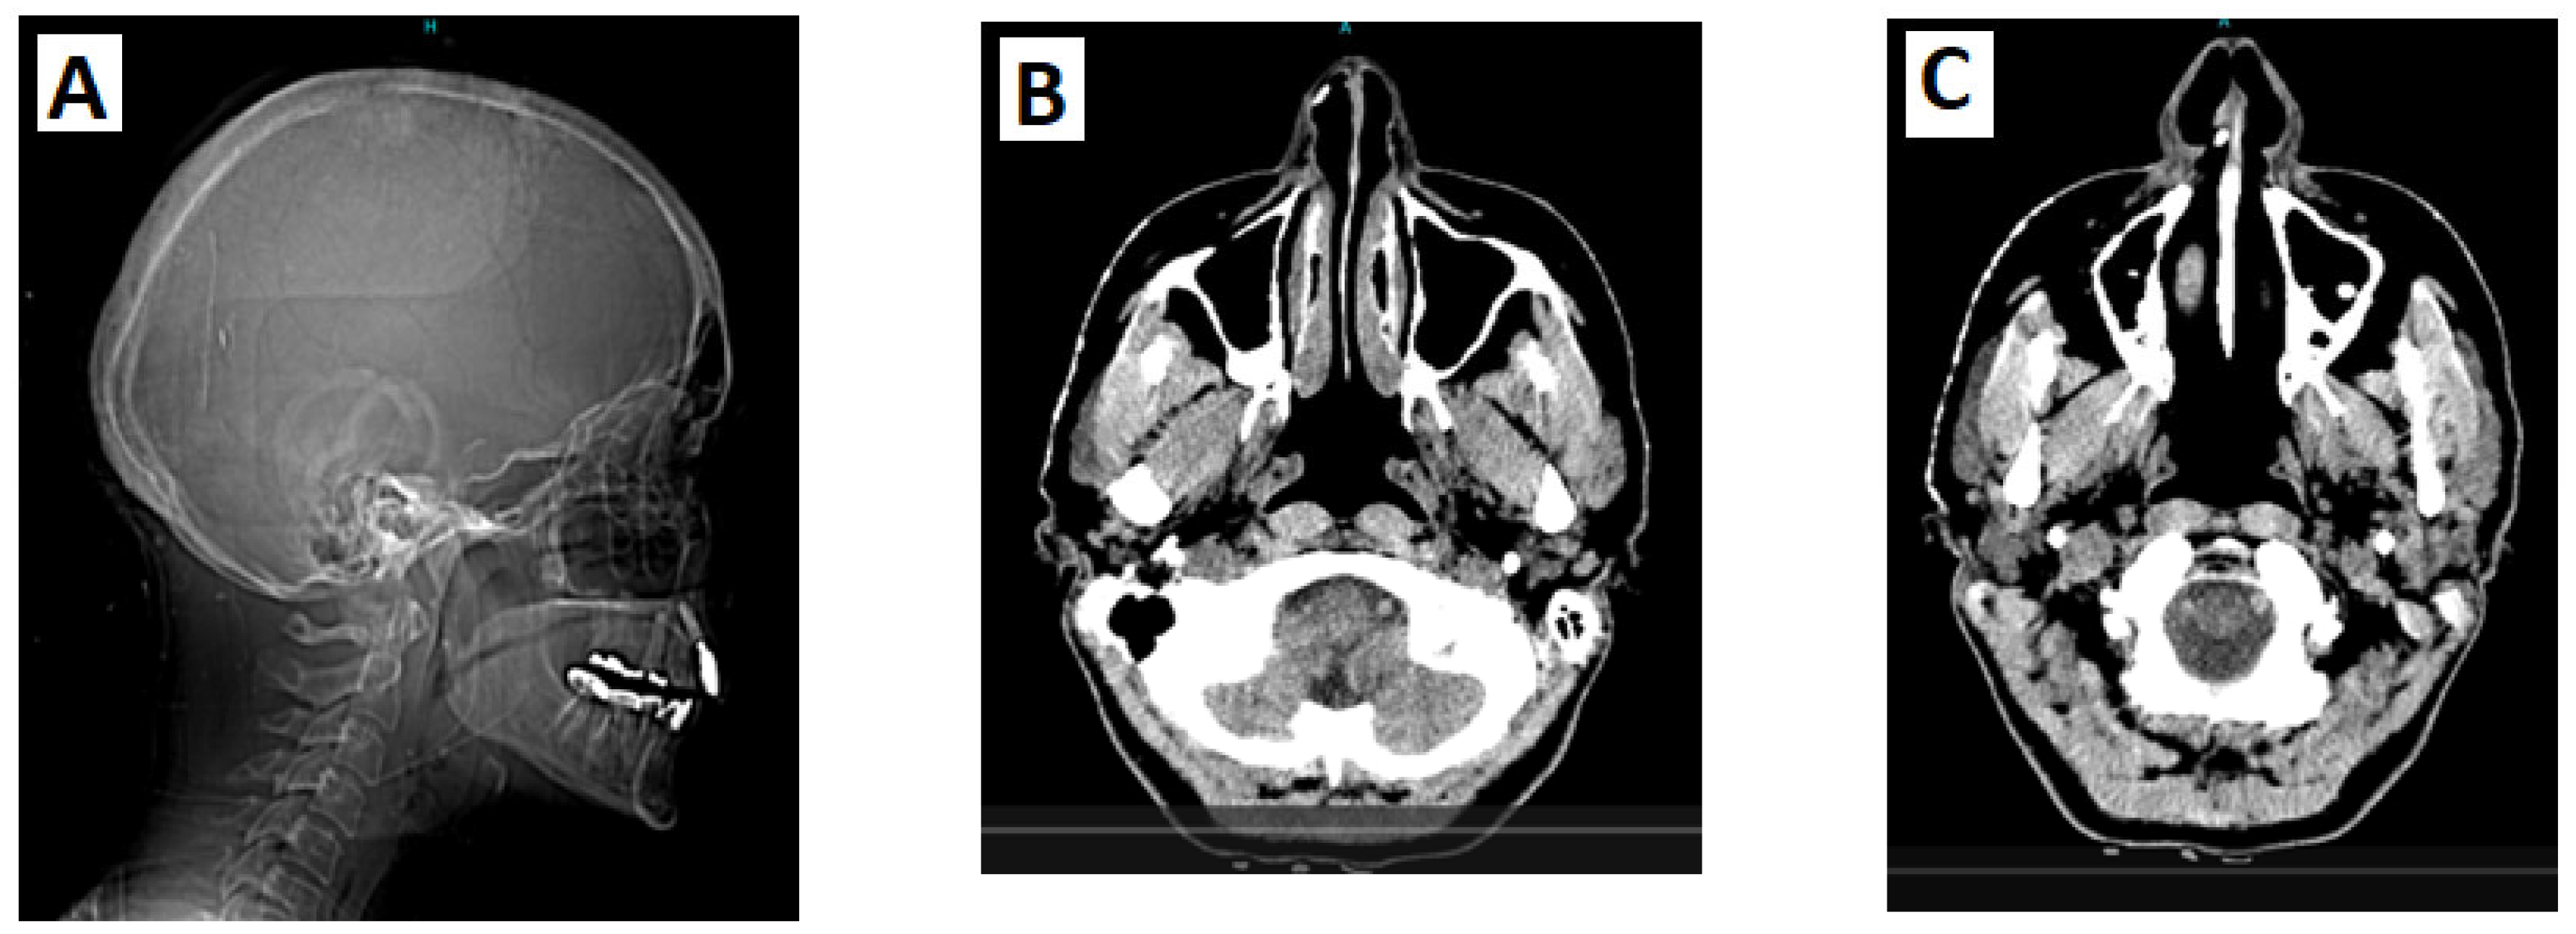

3.1. Case Report